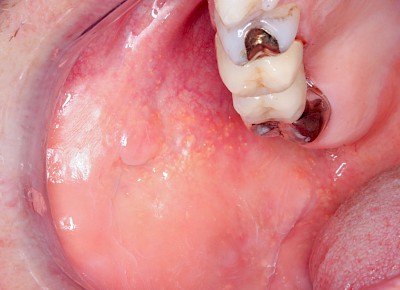

Talgdrüsen

Talgdrüsen sind wichtig für die Haut und machen diese widerstandsfähig gegen Reibungen aller Art. Die Schleimhaut jedoch braucht keine Talgdrüsen, da der Speichel die Oberfläche gut befeuchtet und damit gegen Reibung schützt. Trotzdem kommen – bei manchen Menschen durchaus sehr ausgeprägt – solche ektopen (außerörtlichen) Talgdrüsen vor. Diese haben keinen Krankheitswert und müssen nicht behandelt werden. Ektope Talgdrüsen zeigen sich häufig flächig verteilt und fallen vor allem auf im Bereich der Wangenschleimhaut oder der Lippen.